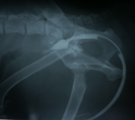

初診時逆行性尿路造影DV像。骨盤外の膀胱に造影剤が貯留していた。 同lateral像。前立腺直前より造影剤が逆流し、前立腺が造影された。 術中所見。会陰ヘルニア整復術。鉗子の先は反転した内閉鎖筋弁。 同。結腸膀胱固定術。下行結腸を左腹壁に固定。膀胱は指で保持。

経過:初診時、直腸温計測できず、心拍数:68/分 呼吸数:28/分。左会陰部が波動感ある著しい腫大を呈していた。試験穿刺を行ったところ尿が360ml採取された。鎮静下にて、尿道カテーテルを介した逆行性尿路造影で前立腺直前に強い抵抗あり尿道内に造影剤が逆流してきた。DV像にてわずかに骨盤外の膀胱に造影剤が貯留しており、lateral像では前立腺管に造影剤が流入し肥大した前立腺が造影された。前立腺直前の尿道が後方に屈曲しヘルニア嚢内に膀胱が嵌頓していることが分かった。排便障害は、前立腺肥大にも原因があると思われた。血液生化学検査でいまだ尿毒症に至っていないことを確認した。ただちに、外科的に左側会陰ヘルニアの整復術、膀胱や結腸嵌頓防止のための腹腔内結腸膀胱固定術、前立腺肥大治療のための去勢術を行った。まず、会陰部切皮前に再度経皮的穿刺し採尿したあと膀胱をヘルニア孔の腹腔側に向け指でできる限り押し入れながら導尿カテーテルを進め、膀胱を環納した。ヘルニア整復は、内閉鎖筋腱を切断し弁状に反転したもの、外肛門括約筋、尾骨筋のそれぞれをマットレス縫合であわせ閉鎖した。結腸膀胱固定術は開腹下にまず下行結腸を左腹壁に3-0Dexonにて4糸の結節縫合にて固定し、その後膀胱の体部を結腸に2糸縫合し反転しないようにした。閉腹後、去勢手術を行った。術後翌日より食欲あり一般状態は改善した。術後8日で痛みなく排便可能となった。飼い主によると、この犬はとても神経質でケージに入ると鳴きわめき、人に咬みつく事があるかもしれないということだったが、手術による整復後、性格は温厚になり、忠実に言うことをきくようになった。術後10日で抜糸完了し退院となった。退院3週間後オーナーより連絡があった。快食快便となり、以前は好物をやっと食べるだけであったが今は何でもすぐに食べ、性格が明るくなった。以前は物陰に隠れたり、人目を盗んで脱走したりするような陰気な性格であったが、退院後そのようなことが全くなくなったという。